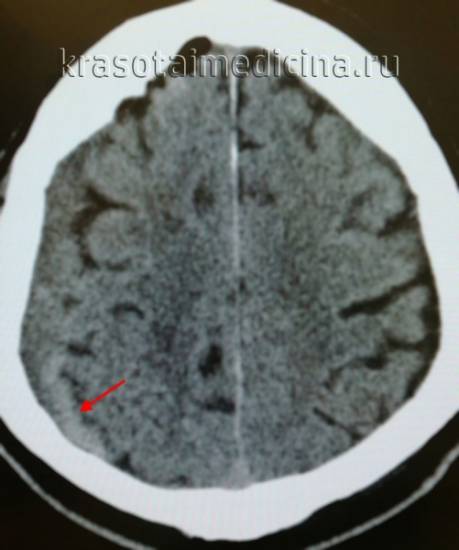

Ключевыми методами диагностики субдуральной гематомы являются КТ и МРТ головного мозга. Для острых гематом предпочтительнее КТ, которая показывает однородную зону повышенной плотности серповидной формы. Со временем гематома разуплотняется, и через 1-6 недель она перестает отличаться по плотности от окружающих тканей. В таких случаях диагноз основывается на смещении латеральных отделов мозга в медиальном направлении и признаках сдавления бокового желудочка.

На компьютерной томограмме можно увидеть:

• острая субдуральная гематома имеет серповидную зону гомогенного повышения плотности;

• гематомы могут быть двусторонними, распространяться в межполушарную щель и на намет мозжечка;

• при разжижении содержимого гематомы и распаде пигментов крови наблюдается снижение ее плотности;

• признаки уменьшения внутричерепных резервных пространств (сужение желудочковой системы, сдавливание конвекситальных субарахноидальных щелей, умеренная или выраженная деформация базальных цистерн);

• развитие дислокационной гидроцефалии может сочетаться с компрессией субарахноидальных пространств.